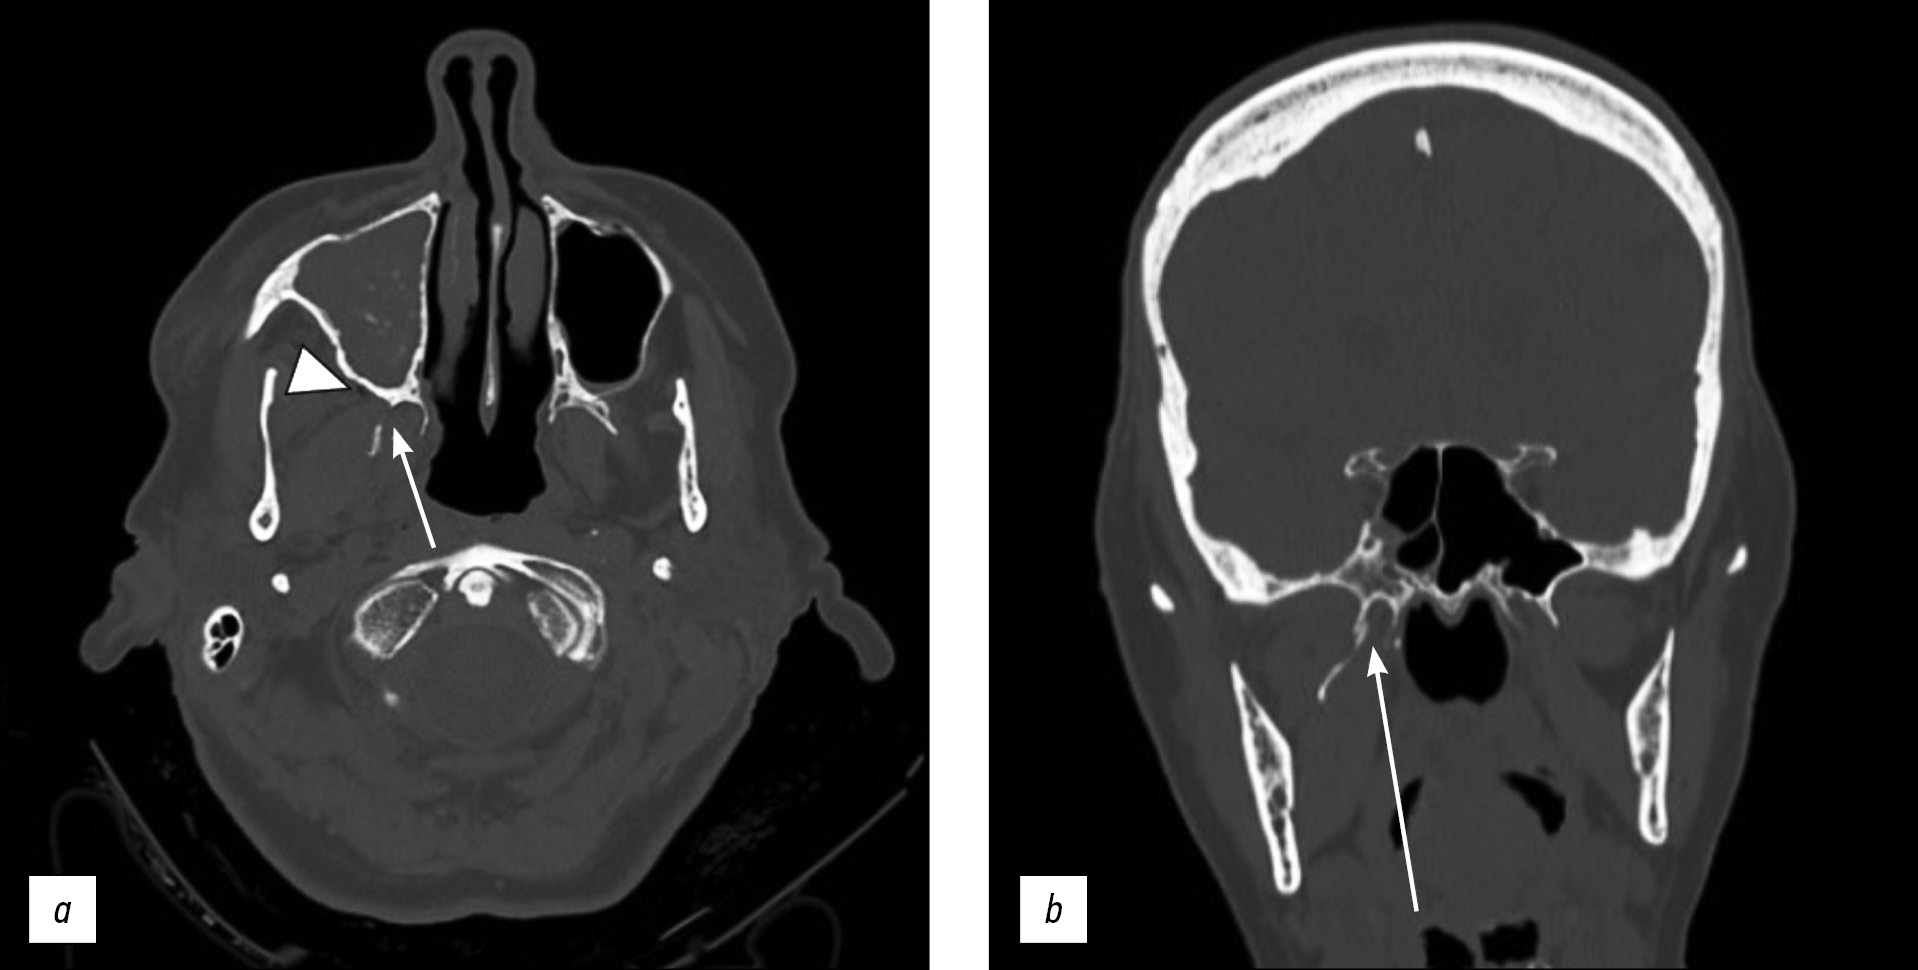

The patient was referred to the radiology department for noncontrast-enhanced high-resolution computed tomography (CT) on a 64-slice scanner, which showed unilateral right pterygoid plate fracture with signs of emphysema in the ipsilateral masticatory space (Fig. 1a, 1b). The CT investigation also documented the fracture of the medial wall of the right maxillary sinus with hemosine (Fig. 2a, 2b, 2c).

Fig 2: Axial (a) and coronal (b) CT scan with bone window documents the fracture of the medial wall of the right maxillary sinus (arrows). Soft window (c) shows hemosine in the right maxillary sinus (arrowhead).